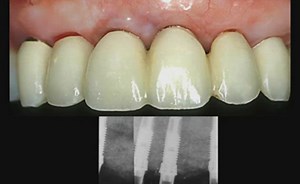

- Ridge Augmentation

Surgery - Dental Implants Bone

Augmentation - Ridge Augmentation